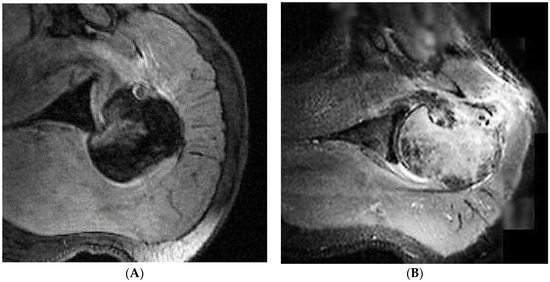

| 1 CP | M–49 | 19 days | 22 days | Hill–Sachs reverse lesion <50% | McLaughlin technique Subscapularis tendon transfer |

| 2 DF | F–49 | 70 days | 106 days | Hill–Sachs reverse lesion <50% | Subscapularis tendon transfer |

| 3 AA | M–54 | 6 days | 14 days | Hill–Sachs reverse lesion <50%, humeral insertional detachment of ST and LHB | Subscapularis tendon transfer |

| 4 CI | M–34 | 2 days | 9 days | Hill–Sachs reverse lesion <50% | Repair through a plication of subscapularis tendon (McLaughlin modified technique) |